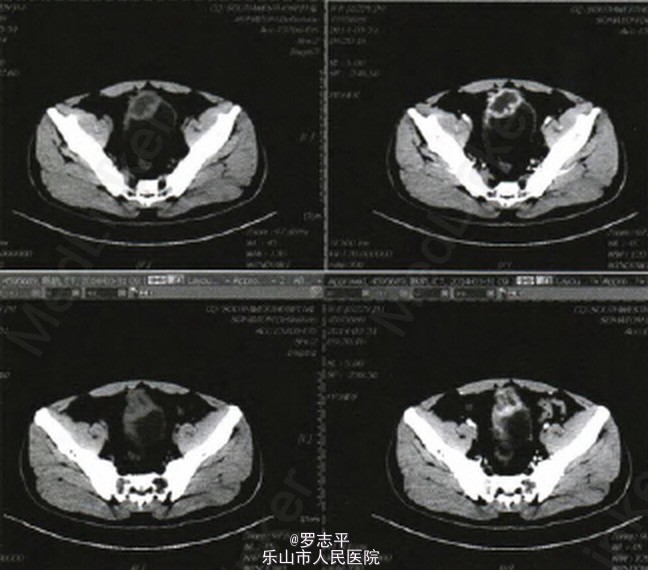

看到一例和交叉普外科和泌尿外科的病例,本来在很多医院这两个科室也是不分的,所以PO在这里给大家分享下。 患者,男,22岁。病史:腹腔镜下阑尾切除术后2年余,阑尾病检结果提示:阑尾坏疽。术后腹部切口反复感染1年余,经加强切口换药后,腹部切口愈合。现已康复半年余。20天前出现尿频、尿急、尿痛就诊于我院。入院后膀胱超声提示:膀胱前壁低回声,性质待定(图1)。CT检查提示:膀胱顶部占位;膀胱癌?(图2)。门诊膀胱镜检查发现膀胱顶部3 cm×3 cm×3 cm大小类圆形占位,表面滤泡样改变,基底部较广。取病理活检提示:(膀胱顶部)送检少许破碎组织显示尿路上皮增生(送检组织较少)。 患者入院后于2014年4月15日在全麻下行经尿道膀胱占位活检术。术中冷冻活检结果提示:慢性膀胱炎。故改行膀胱部分切除术,术中见肿物位于膀胱顶部,膀胱外腹膜质地硬,呈增殖样改变,盆腔内大网膜、肠壁及腹膜相互粘连严重。将肿物及局部腹膜一并切除。术后病检结果提示:(膀胱)慢性肉芽肿性炎伴微脓肿形成。